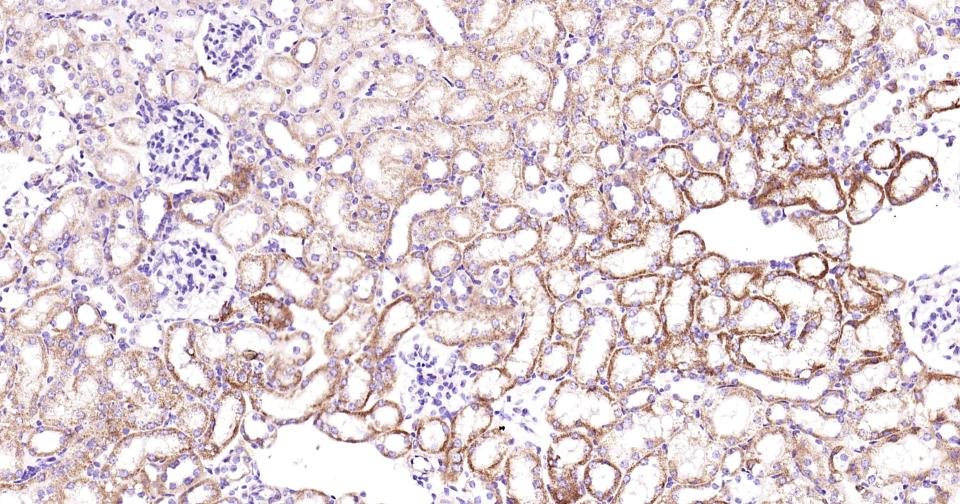

Paraformaldehyde-fixed, paraffin embedded Human Kidney; Antigen retrieval by boiling in sodium citrate buffer (pH6.0) for 15 min; Antibody incubation with PIK3C3 Monoclonal Antibody, Unconjugated(bsm-61161R) at 1:200 overnight at 4°C, followed by conjugation to the SP Kit (Rabbit, SP-0023) and DAB (C-0010) staining.